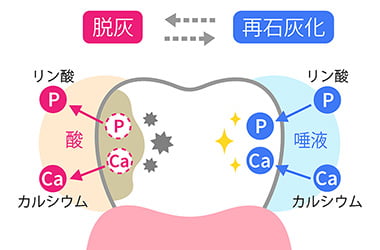

ステファンカーブは、お口のなかのペーハーが変わる様子を表したグラフです。お口のなかはもともと中性の状態ですが、飲食後は酸性に傾き、菌が活性化しやすい環境になります。

このため間食が多い方が虫歯になりやすいです。磨き残しがある場合も酸性の状態が長く続くため、虫歯に注意しなくてはなりません。おやつは、お口の健康を守るために適したものを選ぶことで、ある程度リスクを抑えることができます。